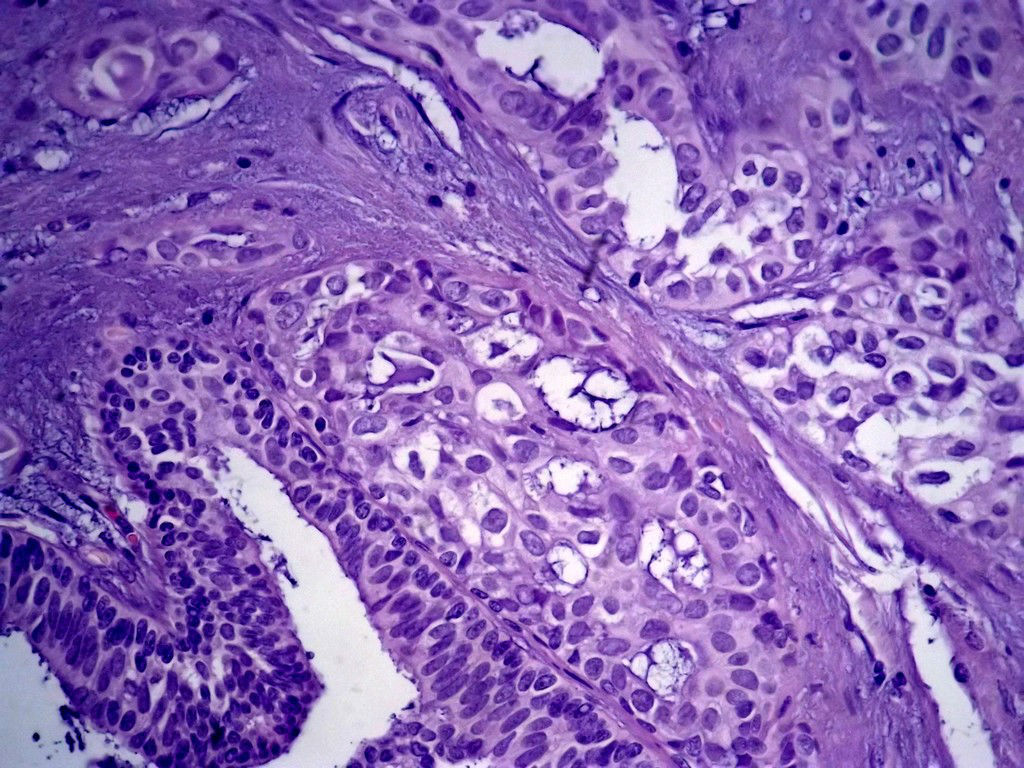

今天的一例术中冰冻。女,49岁,乳腺肿块。人气不旺,换个标题

腺病?癌?其他?(12楼常规,24楼免疫组化及会诊结果)图1

标签:浸润性导管癌 分泌癌 硬化性腺病

乳腺分泌型癌

导管是乎可见双层上皮,部分上皮增生并有一定异型,考虑硬化性腺病,待石蜡。

导管可见双层上皮,部分上皮增生并有一定异型,考虑硬化性腺病

腺体与腺体之间的对比差异太大,不放心,不除外是癌,如果是我的病例,再次取材冰冻

浸润性导管癌。冰冻切片的诊断是很困难,直接诊断癌风险很大,但是在明显正常的导管间这种成片、成巢有腔的细胞团块也不是良性的表现,有的还似乎有围绕正常导管生长的倾向。诊断ADH还可以,但是不能归到任何一种DCIS的生长方式里。这例值得我好好学习。